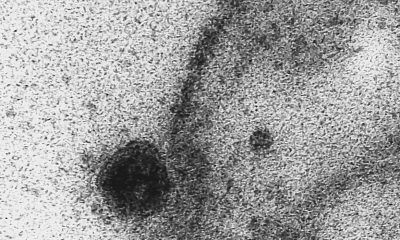

Estudo desenvolvido por pesquisadores da Universidade de São Paulo (USP) mostra que o novo coronavírus (SARS-CoV-2), causador da covid-19, infecta e se replica em células das...